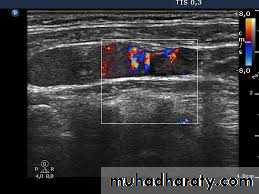

Doppler Ultrasound:

It is used to detect and measure the rate of movement of any fluid such as blood.in "color Doppler'" the direction of flowing blood is distinguished by different colors.

3. Vascular abnormalities (Doppler US)